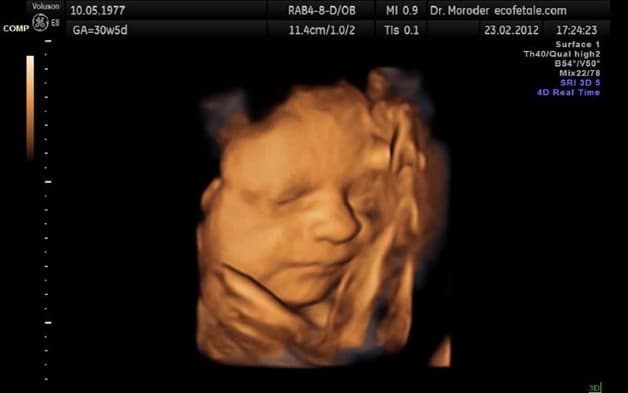

Siêu âm 4D hay còn được gọi là phương pháp siêu âm 4 chiều, đây là kỹ thuật siêu âm thai tiên tiến giúp cung cấp cho chúng ta những hình ảnh chuyển động thực tế của thai nhi bên trong bụng mẹ tại thời gian tiến hành siêu âm.

Cùng với sự phát triển vượt bậc của nền y học hiện đại, kỹ thuật siêu âm 4D đã được cải tiến và bước lên một tầm cao mới. Từ những hình ảnh siêu âm có màu đen trắng như trước đây thì bây giờ siêu âm 4D giúp cung cấp hình ảnh màu với độ sắc nét cao hơn rất nhiều và cử động của thai nhi cũng được hiển thị trên màn hình siêu âm một cách rõ ràng nhất.

Siêu âm 4D hay còn được gọi là phương pháp siêu âm 4 chiều, giúp cung cấp cho chúng ta những hình ảnh chuyển động thực tế của thai nhi bên trong bụng mẹ

Ví dụ dễ hiểu nhất đó là khi siêu âm 4D thì các bác sĩ có thể chụp được mặt cũng như các bộ phận khác của thai nhi một cách rất rõ ràng, thậm chí mẹ còn quan sát được cử động em bé như là đạp, nhảy, ngáp, mút tay… Trên thực tế, đấy chỉ là một ứng dụng nhỏ của phương pháp siêu âm 4D mà thôi, bởi vì với các dòng máy siêu âm hiện đại như ngày nay có khả năng cung cấp rất nhiều phần mềm xem cấu trúc bộ xương, tái tạo lại các mặt cắt khác nhau để giúp bác sĩ quan sát tốt hơn. Ngoài ra, còn có thể sử dụng các phần mềm đặc biệt để siêu âm tim, não và thần kinh cho bé